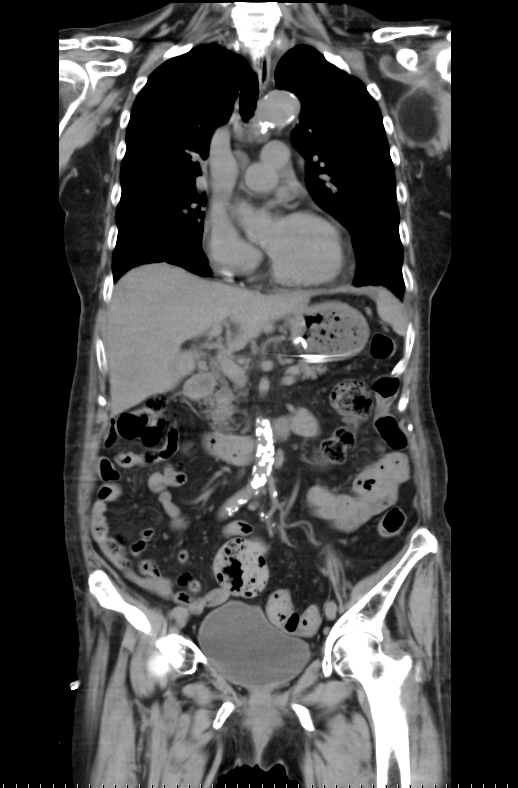

撮影された画像データを⽤いて、様々な⾓度から体を観察できます。よく使われるのは、体を横からみた⽮状断(サジタール画像)、体を正⾯からみた冠状断(コロナール画像)です。また3D画像も作成可能です。⼿術や検査結果の説明に使⽤されています。